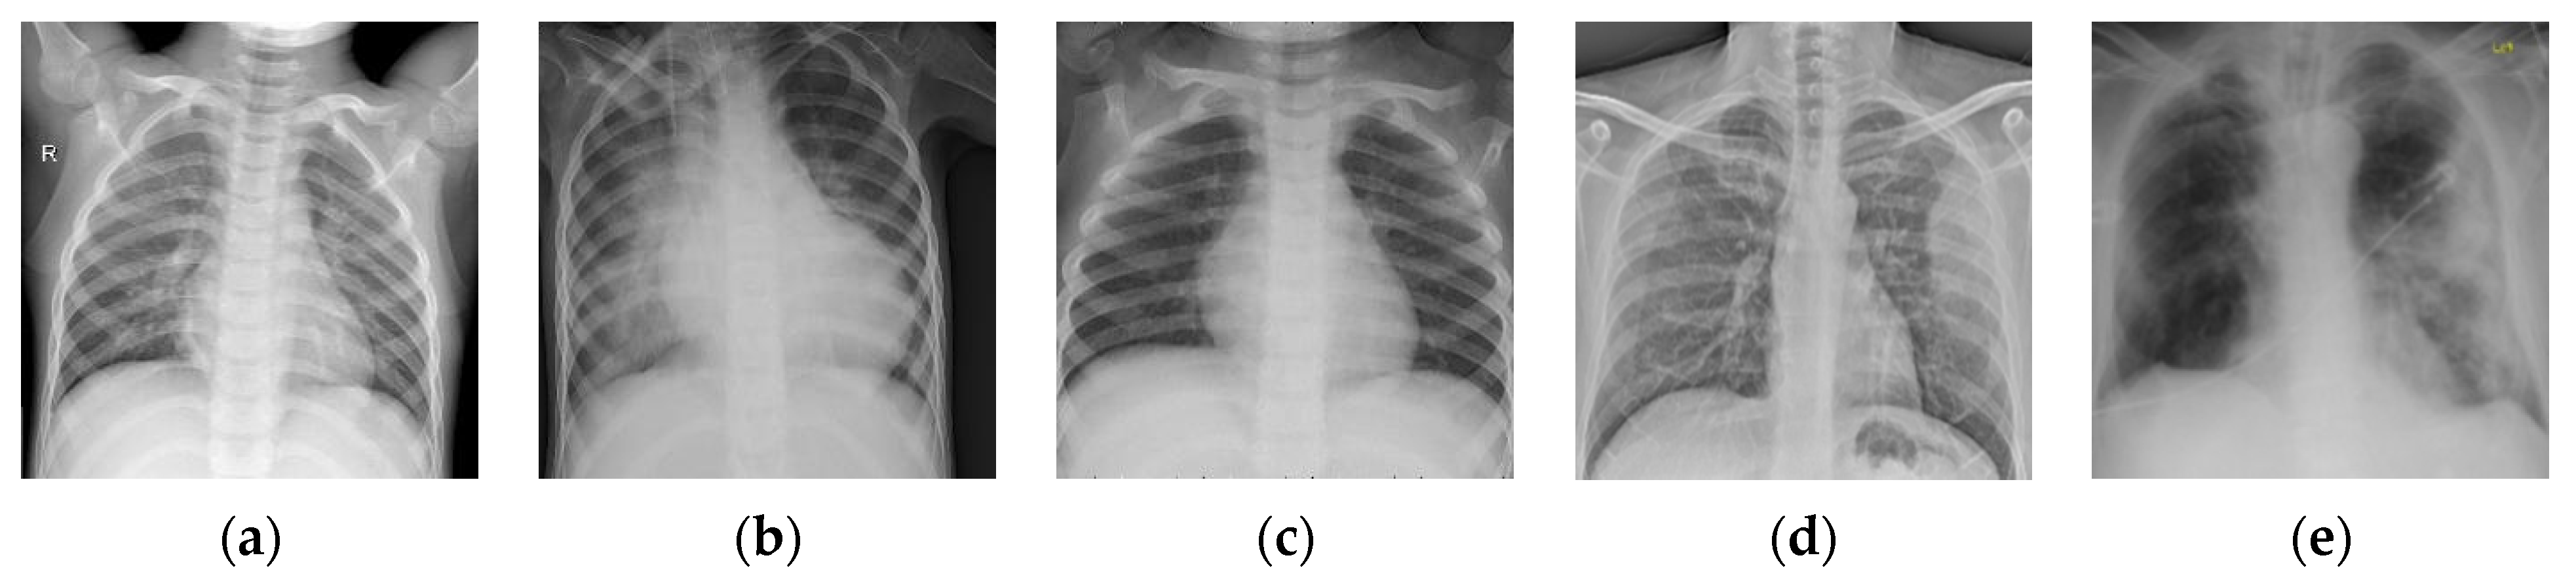

Figure 4.

Examples of the Chest-1 dataset. (a) Normal; (b,c) pneumonia; (d,e) COVID-19.

3.2. The Influence of

The number of images in one batch is an important parameter in the calculation of the BSTriplet loss, because it can influence the similarity matrix and further affect the estimation for training data distribution. Besides this, it has an impact on the stability of the training process. To explore the influence of , we have downloaded a dataset of chest X-ray images [41,42] from the Kaggle [43] website. This dataset is denoted as “Chest-1” for brevity in the following. For this dataset, the X-ray images will be classified into three classes, including normal, (regular) pneumonia, and COVID-19. Several examples are shown in Figure 4. Here, these images are cropped to squares for better clarity. All the images are resized as to be input into the network, and the construction of the Chest-1 dataset is shown in Table 2. According to the data mining strategy described above, we cluster the images in the Chest-1 dataset into six groups by K-means [44], wherein there are two groups for each class. Based on the ratios of groups, we have sampled each group to build different sizes of input batches . ModbileNet-V3-Small is used as the base framework and is trained by CE loss combined with the proposed BSTriplet loss. Some experiments have been performed with various , while other hyper-parameters are fixed according to the method of controlling variables. The accuracy () is adopted as a metric to evaluate the performance, which is defined as: